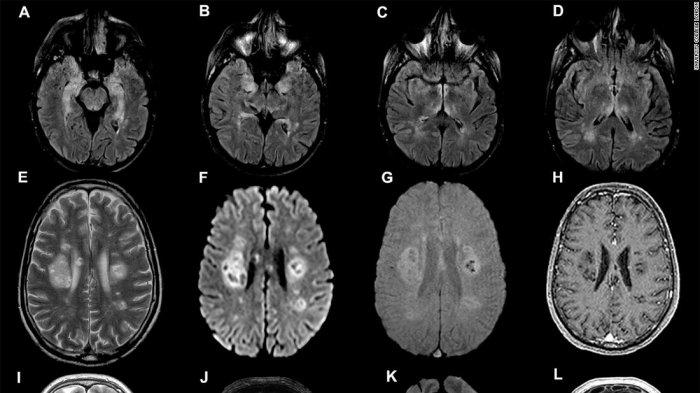

Sebuah studi yang dikerjakan para peneliti di University College London (UCL) menggambarkan, 43 kasus pasien Covid-19 menderita disfungsi otak sementara, stroke, kerusakan saraf atau efek otak serius lainnya.

Lebih jauh, dalam studi UCL, yang diterbitkan dalam jurnal Brain, sembilan pasien yang mengalami peradangan otak didiagnosis dengan kondisi langka yang disebut akut.

Kondisi ini disebarluaskan ensefalomielitis (ADEM) yang lebih sering terlihat pada anak-anak dan dapat dipicu oleh infeksi virus.

Tim mengatakan, biasanya akan melihat sekitar satu pasien dewasa dengan ADEM per bulan di klinik spesialis mereka di London.

Namun, jumlah pasien dilaporkan telah meningkat.